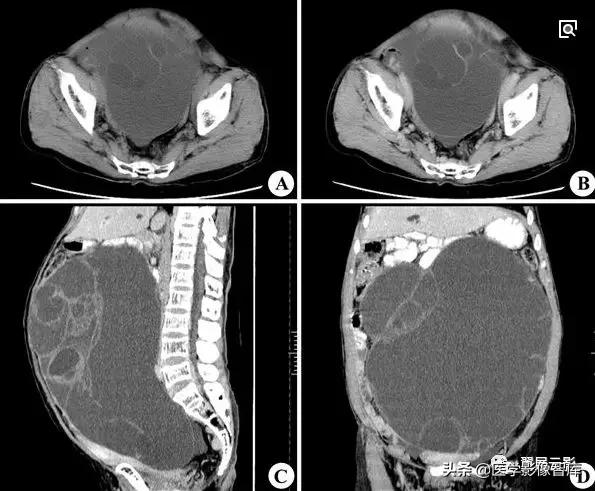

卵巢囊腺瘤

本病分为浆液性囊腺瘤和黏液性囊腺瘤,约占卵巢原发肿瘤的1/4,双侧发生率约为15%,浆液性囊腺瘤和黏液性囊腺瘤可以并存,浆液性囊腺瘤呈单房或多房改变,黏液性囊腺瘤多为多房改变,好发年龄为20—50岁,临床症状有腹部不适或隐痛,腹部包块等,少数伴有月经紊乱,浆液性囊腺瘤患者有时可出现腹水,病理表现:肿瘤切面为单房或多房性,囊壁光滑或有乳头状突起,浆液性囊腺瘤囊壁上皮为单层立方或矮柱状上皮;黏液性囊腺瘤囊壁上皮为单层黏液柱状上皮。

右侧卵巢粘液性囊腺瘤

注意观察描述卵巢囊腺瘤的大小及均匀液性长T1,长T2信号特点,同时应观察描述囊腺瘤的分隔和乳头状壁结节,一般在T2WI上显示清晰,黏液性囊腺瘤内有粘蛋白,T1WI呈等或略高信号,T2WI为高信号,此点可与浆液性囊腺瘤相鉴别。